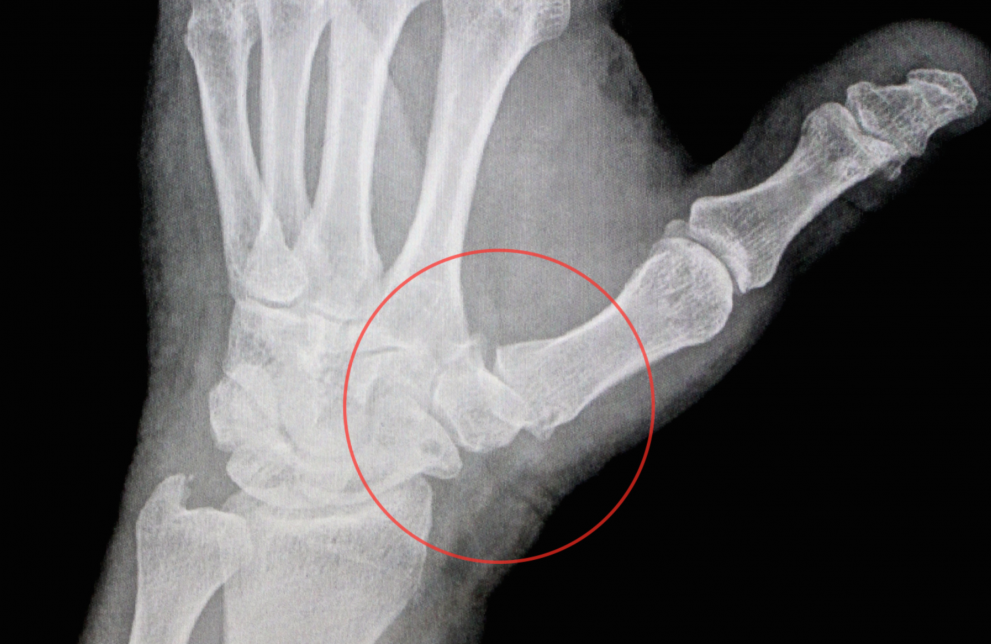

Značilna je bolečina v predelu sklepa, ki je izrazitejša ob določenih gibih (odpiranje kozarcev, odklepanje vrat, pisanje) in ob pritisku na obolelo področje. S časom se zmanjša obseg gibljivosti v sklepu, bolečina pa postane stalna in se pojavi tudi ponoči. Pri nepredovalih oblikah bolezni se sklep delno izpahne, kar se pokaže z izboklino v predelu sklepa in spremenjenim položajem palca, ki je primaknjen k dlani. Posledično se prekomerno iztegne srednji palčev sklep in palec dobi značilno obliko črke Z. Diagnozo potrdimo s posebnimi testi in retngenskim slikanjem.